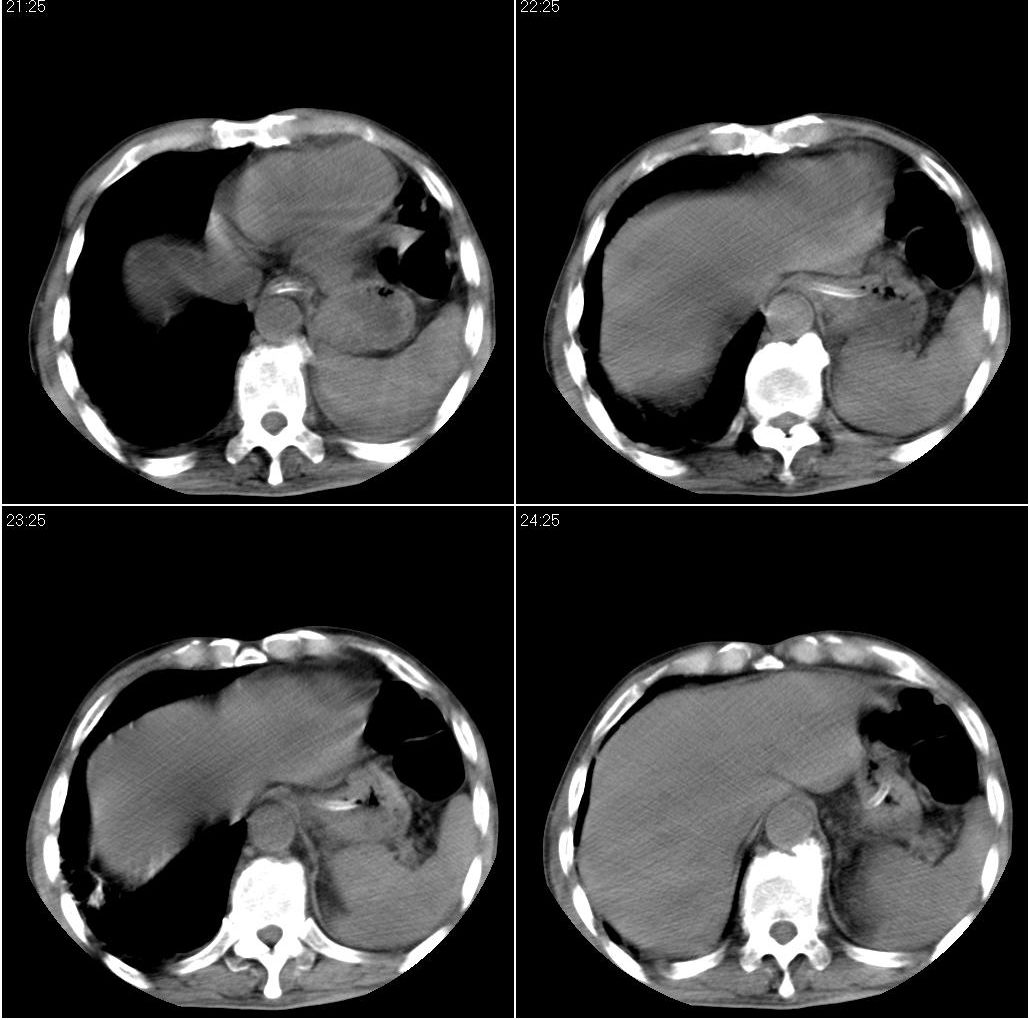

男性,65岁。因外伤来诊。该患者因脑外伤住院。以下是今天的dr和ct:

一周前胸片无异常,不考虑肿瘤,现x片及ct表现应与外伤有关,考虑左侧外伤性膈疝,并左下肺不张。右肺挫裂伤。少量胸水。

一周前胸片无异常,不考虑肿瘤,现x片及ct表现应与外伤有关,考虑左侧外伤性膈疝,并左下肺不张。右肺挫裂伤。少量胸水。支持

1 外伤性左侧膈疝、胸腔积液致左肺下叶不张 2右肺挫伤

右侧第7肋骨腋段骨折并右肺挫伤;左侧膈疝并肺不张。

左下肺叶阻塞性肺不张.左侧少量胸腔积液. 左侧膈疝可能性大,建议食道造影检查!